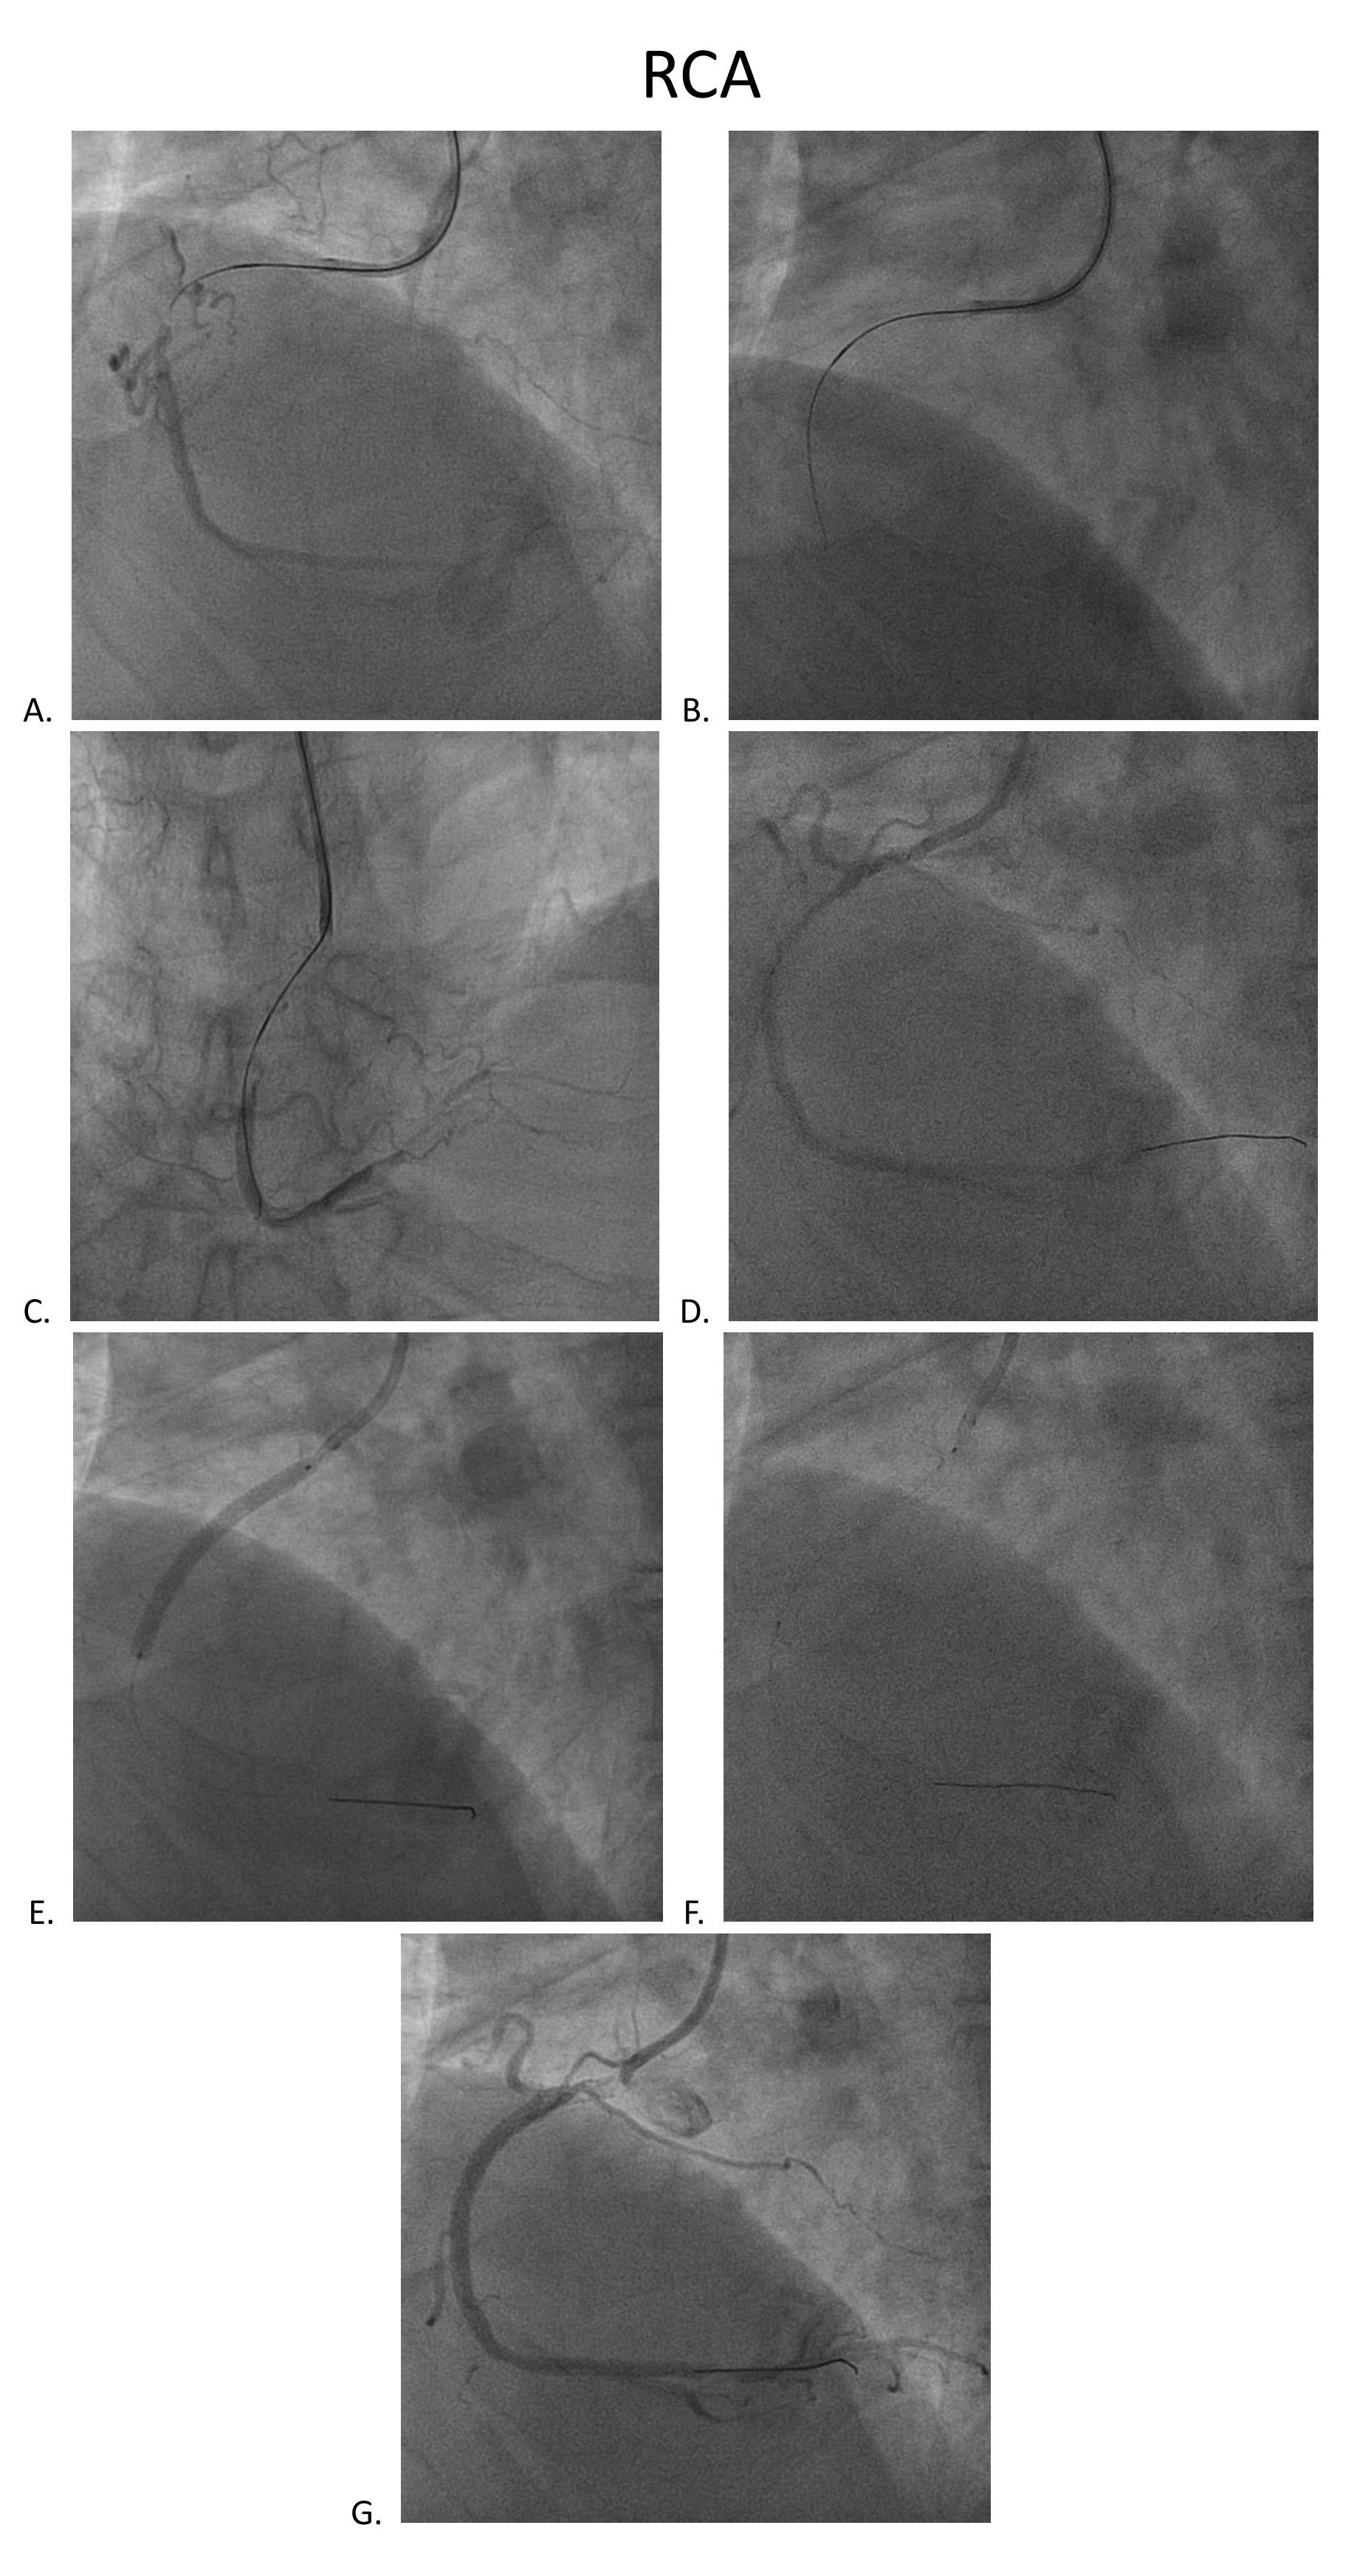

Coronary angiography disclosed orifice total occlusion with TIMI grade 0 antegrade flow at LAD, middle total occlusion at LCX, and RCA proximal total occlusion with auto-collateral to RCA distal.

SCR guiding cath was used to engage RCA. Runthrough wire, Conquest pro, and Conquest 860 wire were used to get cross the CTO lesion. Resolute 2.75x38mm stent was inflated after predilatation with different size BC. XB 3.0x6fr guiding cath was used to engage LCX. Sion blue, Conquest pro, and Fielder XT-A wire were used to get cross the LCX lesion. Predilatation was done with 1.5x20mm BC, followed by Sierra 2.0x38mm stenting and 2.0x30mm B. Braun DEB.